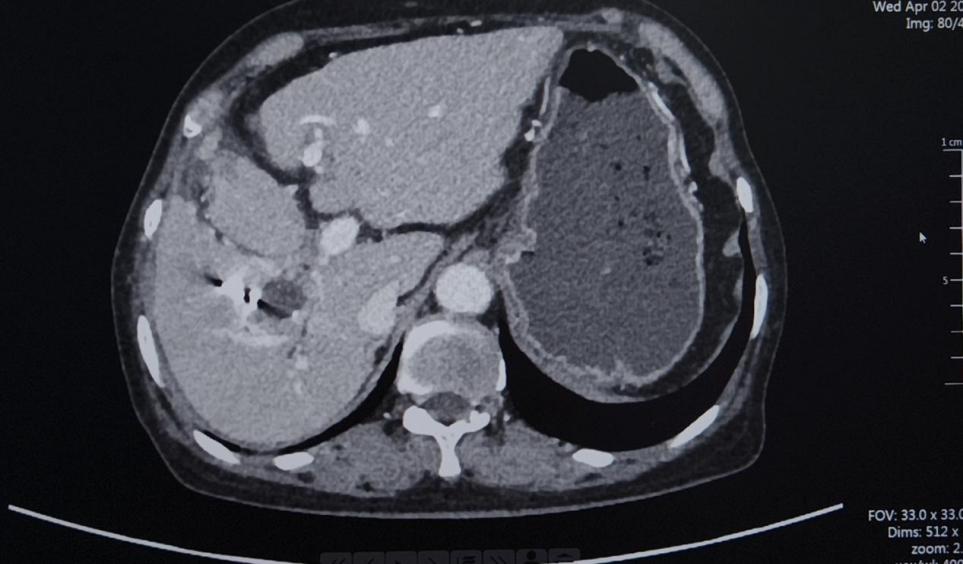

CT(2025.2.18):1、肝右叶异常强化团块影伴周围胆管扩张,考虑肝内胆管癌可能性大,门静脉右支充盈缺损影,考虑癌栓形成。2、脾脏缺如;胆囊、胰腺、双肾及双侧肾上腺未见明显异常

TACE术后28天影像学检查

与2025-02-18日腹部增强片对比示:1.肝右叶多发低密度结节,考虑胆管癌,最大病变内多发颗粒状致密影,考虑介入术后改变,较前病变内坏死增多。肝中静脉局部走行于病灶边缘,管腔未见明显受侵。2.门脉右支起始处少许癌栓,远端未见显影,考虑治疗后改变。3.脾脏缺如;胆囊继发性改变,胆囊窝积液。肠系膜间可见多发稍大淋巴结。